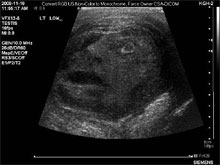

Сотрудники Медицинской школы Университета Квинс, делая ультразвук опухоли, были немало удивлены. С экрана на них смотрело четко различимое человеческое лицо, пишет The Star.

Как сообщает портал, доктора Надзи Тоума и Грегори Робертс просматривали изображения опухоли яичка пациента. Именно тогда они увидели настоящее лицо. По словам специалистов, "лицо" имело такое выражение, будто кто-то кричал в агонии. Его рот был раскрыт, а один глаз выбит.

Известно, что снимок принадлежит 45-летнему мужчине, который обратился к врачу с жалобами на дискомфорт. Специалисты выявили у него доброкачественное новообразование размером в 6 сантиметров. По их словам, опухоль появилась в результате перенесенной инфекции.

В итоге врачам пришлось удалить пораженное яичко. Как подчеркивают специалисты, им ни разу не приходилось видеть подобную опухоль за всю свою врачебную практику. Однако это всего лишь стечение обстоятельств, а не некий знак свыше.